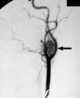

Carotid body tumor

A paraganglioma is a rare neuroendocrine neoplasm that may develop at various body sites (including the head, neck, thorax and abdomen). When the same type of tumor is found in the adrenal gland, they are referred to as a pheochromocytoma. [Source: Wikipedia ]